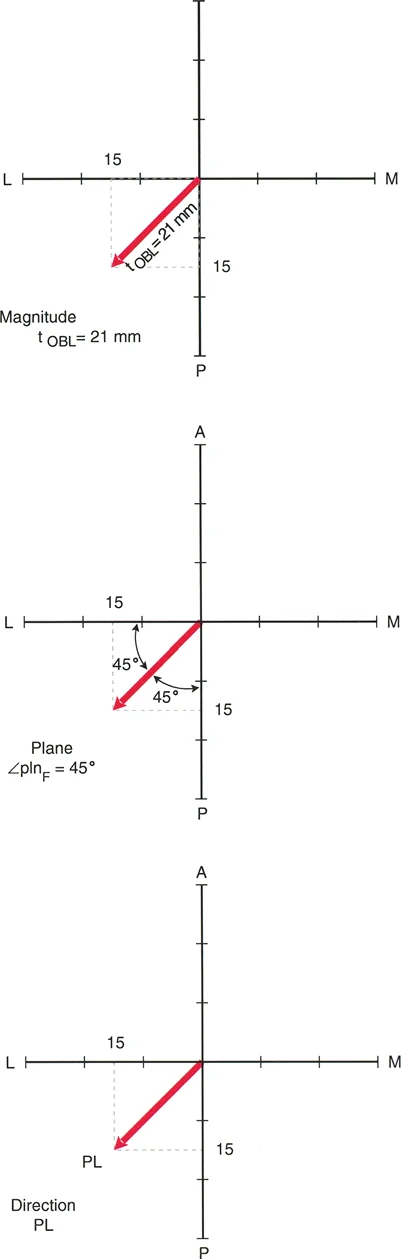

3. الرسوم البيانية للانزياح (Translation Graphs)

يستخدم الأستاذ الدكتور محمد هطيف رسوماً بيانية خاصة لتحليل تشوهات الانزياح، خاصة تلك التي تحدث في المستويات المائلة. هذه الرسوم البيانية تساعد في:

* تحديد الاتجاه الدقيق: مثل الاتجاه الأمامي-الخلفي (AP) أو الإنسي-الوحشي (LAT) أو مزيج منهما (Posterolateral - PL).

* قياس الحجم بدقة: تسمح بقياس حجم الانزياح بالمليمترات، حتى في المستويات المعقدة.

* تحديد مستوى الانزياح: المسافة من المفصل القريب إلى مستوى التداخل.